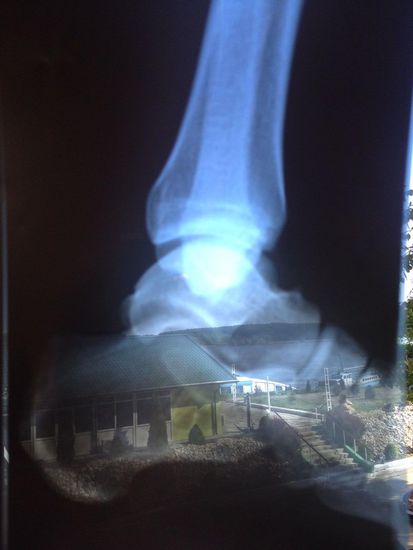

Die schwarze GS diente, inzwischen blitzeblank geputzt, als Krankentransporter und fuhr Norbert vom Krankenhaus zur Apotheke, um diverse Medikamente einzukaufen, die der Doc verschrieben hatte und die es aus seiner Sicht möglich machen sollten, trotz eines alten Risses im Fußknochen vorsichtig weiterzufahren - schau mehr mal!

Hier das Röntgenbild mit der Diagnose, das ab morgen unserem Trip nichts mehr im Wege steht... Hurra, unser Norbert ist wieder einsatzfähig. Die Silhouette ist unser Hotel mit direktem Blick auf den Nebenarm der Donau.